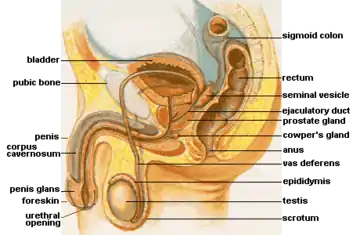

Male anatomy and reproductive system

Males also have both internal and external genitalia that are responsible for procreation and sexual intercourse. Production of spermatozoa (sperm) is also cyclic, but unlike the female ovulation cycle, the sperm production cycle is constantly producing millions of sperm daily.[16]

External male anatomy

The male genitalia are the penis and the scrotum. The penis provides a passageway for sperm and urine.[24] The penis consists of nerves, blood vessels, fibrous tissue, and three parallel cylinders of spongy tissue.[25] Other components of the penis include the shaft, glans, root, cavernous bodies, and spongy body.[25] The three cylindrical bodies of spongy tissue, which are filled with blood vessels, run along the length of the shaft.[25] The two bodies that lie side by side in the upper portion of the penis are the corpora cavernosa (cavernous bodies).[25] The third, called the corpus spongiosum (spongy body), is a tube that lies centrally beneath the others and expands at the end to form the tip of the penis (glans).[25]

The raised rim at the border of the shaft and glans is called the corona.[26] The urethra connects the urinary bladder to the penis where urine exits the penis through the urethral meatus.[27] The urethra eliminates urine and acts as a channel for semen and sperm to exit the body during sexual intercourse.[27] The root consists of the expanded ends of the cavernous bodies, which fan out to form the crura and attach to the pubic bone and the expanded end of the spongy body.[28] The bulb of the penis is surrounded by the bulbospongiosus muscle, while the corpora cavernosa are surrounded by the ischiocavernosus muscles.[29] These aid urination and ejaculation.[30] The penis has a foreskin that typically covers the glans; this is sometimes removed by circumcision for medical, religious or cultural reasons. In the scrotum, the testicles are held away from the body, one possible reason for this is so sperm can be produced in an environment slightly lower than normal body temperature.

The penis has very little muscular tissue, and this exists in its root.[31] The shaft and glans have no muscle fibers. Unlike most other primates, male humans lack a penile bone.[25]

Internal male anatomy

Male internal reproductive structures are the testicles, the duct system, the prostate and seminal vesicles, and the Cowper's gland.[16]

The testicles (male gonads), are where sperm and male hormones are produced. Millions of sperm are produced daily in several hundred seminiferous tubules. Cells called the Leydig cells lie between the tubules; these produce hormones called androgens; these consist of testosterone and inhibin. The testicles are held by the spermatic cord, which is a tubelike structure containing blood vessels, nerves, the vas deferens, and a muscle that helps to raise and lower the testicles in response to temperature changes and sexual arousal, in which the testicles are drawn closer to the body.[16]

Sperm gets transported through a four-part duct system. The first part of this system is the epididymis. The testicles converge to form the seminiferous tubules, coiled tubes at the top and back of each testicle. The second part of the duct system is the vas deferens, a muscular tube that begins at the lower end of the epididymis.[16] The vas deferens passes upward along the side of the testicles to become part of the spermatic cord.[33] The expanded end is the ampulla, which stores sperm before ejaculation. The third part of the duct system is the ejaculatory ducts, which are 1-inch (2.5 cm)-long paired tubes that pass through the prostate gland, where semen is produced.[16] The prostate gland is a solid, chestnut-shaped organ that surrounds the first part of the urethra, which carries urine and semen.[16][33] Similar to the female G-spot, the prostate provides sexual stimulation and can lead to orgasm through anal sex.[34]

The prostate gland and the seminal vesicles produce seminal fluid that is mixed with sperm to create semen.[16] The prostate gland lies under the bladder and in front of the rectum. It consists of two main zones: the inner zone that produces secretions to keep the lining of the male urethra moist and the outer zone that produces seminal fluids to facilitate the passage of semen.[33] The seminal vesicles secrete fructose for sperm activation and mobilization, prostaglandins to cause uterine contractions that aid movement through the uterus, and bases that help neutralize the acidity of the vagina. The Cowper's glands, or bulbourethral glands, are two pea-sized structures beneath the prostate.